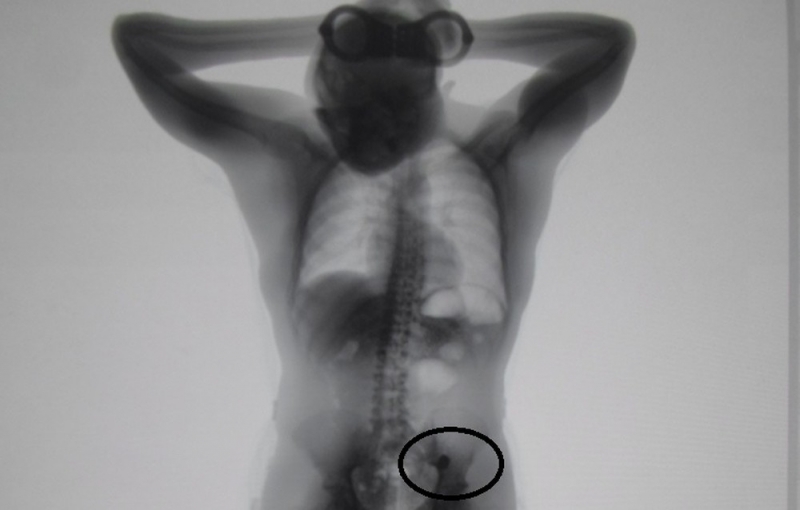

O equipamento de raio-x do Centro de Detenção Provisória (CDP) de Pinheiros IV mostrou duas alianças de casamento no estômago de um assaltante, após ele passar por audiência de custódia.

Segundo a Secretaria da Administração Penitenciária (SAP), o rapaz havia engolido as peças antes de ser preso em flagrante.

Por conta disso, ele ficou isolado na enfermaria até conseguir expelir as alianças, que foram devolvidas para o casal, vítimas do assalto, na sexta-feira (18). Os agentes de segurança penitenciária analisaram os objetos e encontraram os nomes deles e uma data de casamento gravados nas alianças.

Essas informações foram confrontadas com os nomes das vítimas do Boletim de Ocorrência, e os dois foram chamados pela polícia para entrega das joias.